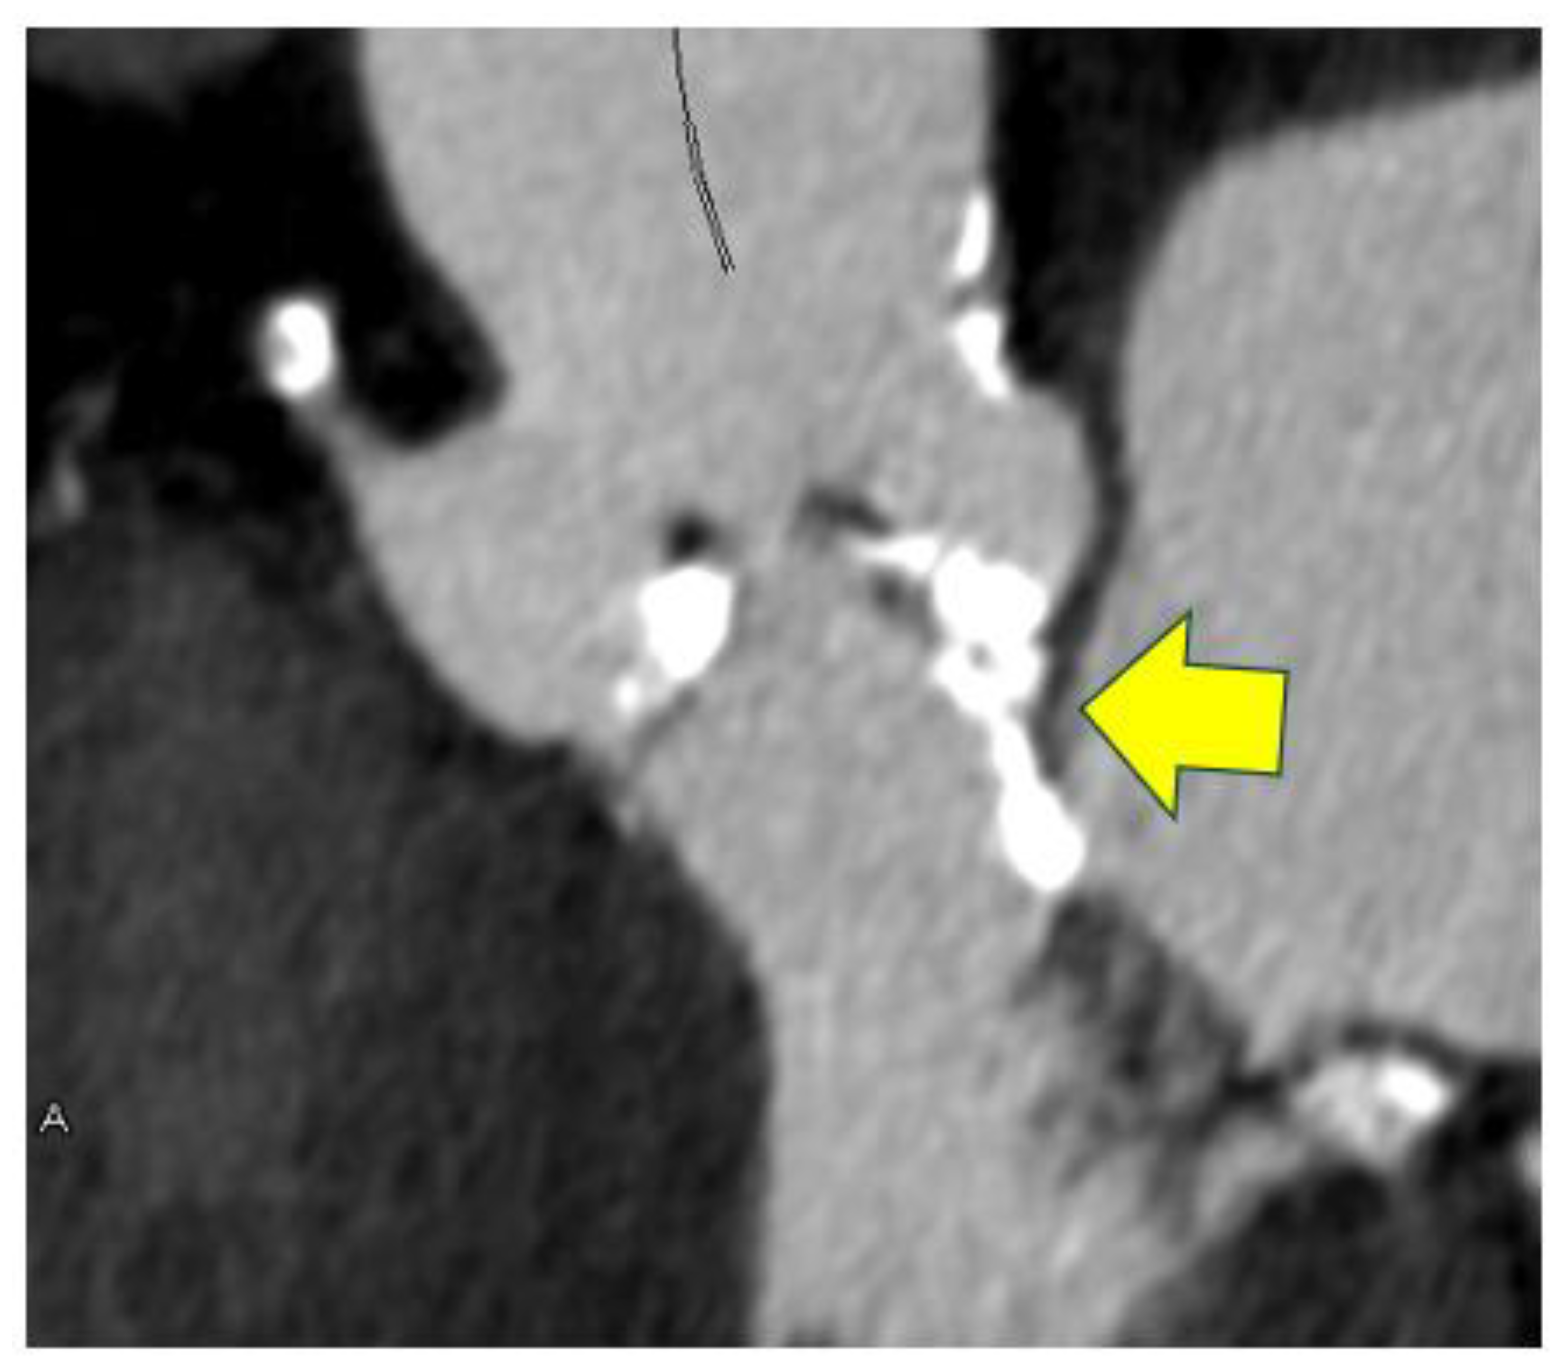

3.4. Utility of the Evaluation of Congenital Abnormalities on Computed Tomography

- Saito, Y.; Takaoka, H.; Funabashi, N.; Ozawa, K.; Tamura, Y.; Saito, M.; Matsumiya, G.; Kobayashi, Y. A case of very severe aortic stenosis due to unicuspid aortic valve mimicking bicuspid aortic valve with calcification on cardiac computed tomography. Int. J. Cardiol. 2016, 215, 516–518. [Google Scholar] [CrossRef]